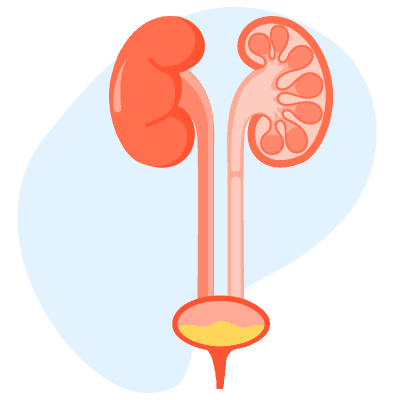

အဓိပ္ပါယ်ဖွင့်ဆိုချက် Thyroid Nodules (သိုင်းရွိုက်အကျိတ်ဖြစ်ခြင်း) ကဘာလဲ။ သိုင်းရွိုက်အကျိတ်ဖြစ်ခြင်းဆိုတာ သိုင်းရွိုက်ဂလင်းထဲမှာ ပုံမှန်မဟုတ်တဲ့ အကျိတ်တွေဖြစ်ပေါ်လာခြင်း ဖြစ်ပါတယ်။ သိုင်းရွိုက်ဂလင်းရဲ့ ပုံမှန်မဟုတ်တဲ့ အစိတ်အပိုင်းတွေ ရောင်ရမ်းကြီးထွားလာခြင်းကို သေချာစွာ မကုသရင် ဖြစ်တတ်ပါတယ်။ တခါတရံ ကင်ဆာလို ဆိုးရွားတဲ့ အခြေအနေတွေကြောင့် ဖြစ်တတ်ပါတယ်။ Thyroid Nodules (သိုင်းရွိုက်အကျိတ်ဖြစ်ခြင်း) က ဘယ်လောက်အဖြစ်များသလဲ တွေ့ရများပါတယ်။ အမျိုးသမီးတွေမှာ ပိုဖြစ်တတ်ပါတယ်။ အသက်အရွယ်မရွေး ဖြစ်တတ်ပါတယ်။ ဖြစ်နိုင်ခြေအန္တရာယ်တွေကို လျှော့ချနိုင်ပါတယ်။ ပိုသိရအောင် ဆရာဝန်နဲ့ တိုင်ပင်ဆွေးနွေးပါ။ လက္ခဏာများ Thyroid Nodules (သိုင်းရွိုက်အကျိတ်ဖြစ်ခြင်း) ရဲ့လက္ခဏာတွေကဘာတွေလဲ သိုင်းရွိုက်ဂလင်းကနေ သိုင်းရွိုက်ဟော်မုန်းကို ထုတ်လုပ်ပါတယ်။ သိုင်းရွိုက်အကျိတ်အများစုဟာ ဟော်မုန်းပမာဏကို မပြောင်းလဲစေနိုင်ပါဘူး။ တခါတရံမှာ ဟော်မုန်းပမာဏကို ပိုပြီး များလာစေတတ်ပါတယ်။ အောက်ပါလက္ခဏာတွေ တွေ့နိုင်ပါတယ်။ စိတ်ပူပန်ခြင်း၊ အနှောင့်အယှက်ဖြစ်ခြင်း၊ အိပ်မပျော်ခြင်း အားနည်းပင်ပန်းခြင်း ကိုယ်အလေးချိန် အလိုလိုကျသွားခြင်း နှလုံးခုန်မြန်ခြင်း အစာအိမ် အူလမ်းကြောင်း မကြာခဏ လှုပ်ရှားခြင်း လူတချို့မှာ […]